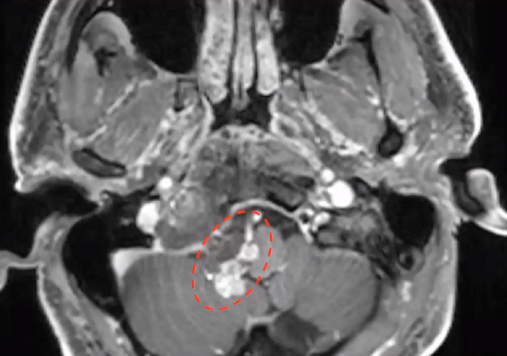

▼下图所示案例肿瘤看着很大,然后用30度、45度甚至70度的内镜,我们有很多带角度的器械,利用这些器械就可以切除肿瘤。可以先切开黏膜,然后把蝶窦内的黏膜推开,然后进入肿瘤。目前我们正在努力的开发这方面的器械,没有这些器械我们是做不了手术的。

▼下面就是我所说的有角度的器械,最后我们用脂肪来修补,我们在内镜下做缝合,在内镜下做缝合很复杂难度很大,所以很花时间,但是它是值得的。

▼这是术后的MRI,大家看到的高信号的是脂肪组织,我觉得利用内镜到达颅颈交界区更简单。